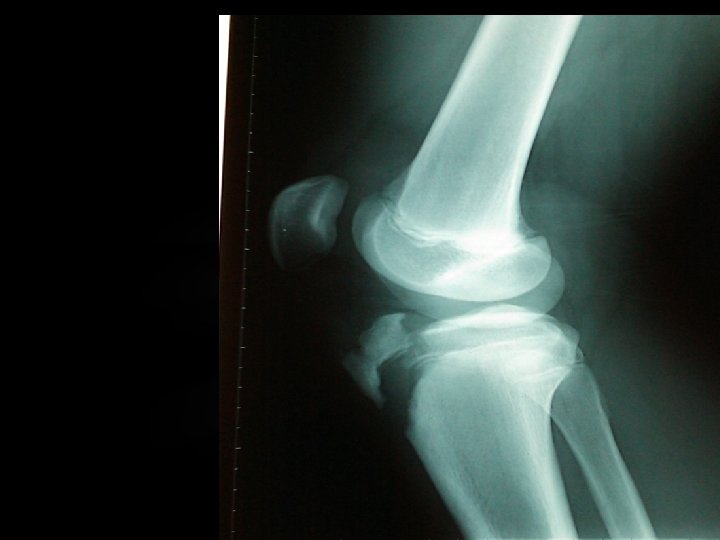

Exploración de rodilla dcha: Dolor en cara anterior con deformidad e impotencia funcional Pruebas complementarias: Rx rodilla dcha Arrancamiento tuberosidad tibial anterior

MECANISMO DE LESIÓN 1. Contracción violenta del músculo cuádriceps manteniendo la tibia fija. Ejempl 0: cuando un depertista salta o aterriza, como en el baloncesto o atletismo 2. Flexión pasiva brusca de la rodilla manteniendo el cuádriceps contraído. Ejemplo: aterrizar mal al terminar el salto

CLASIFICACIÓN Tipo I: Separación a través de la porción distal de la fisis por debajo de la tuberosidad irrumpe proximalmente a través del núcleo de osificación de la tuberosidad

CLASIFICACIÓN Tipo II: La separación se extiende anteriormente a través del área que puentea los núcleos de osificación de la tuberosidad tibial y de la epífisis proximal de la tibia

CLASIFICACIÓN Tipo III: La separación por debajo de la tuberosidad se propaga proximalmente a través de la epífisis proximal de la tibia hasta la rodilla por debajo de la inserción anterior de los meniscos